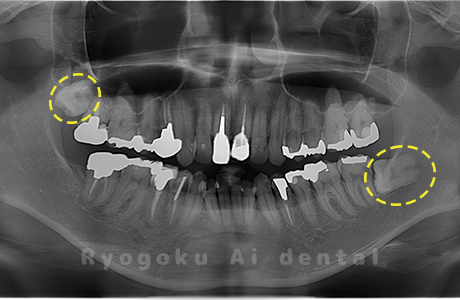

Case02

-

- 原因

- 下顎の水平埋伏智歯

- 治療内容

- 下顎の水平埋伏智歯を抜歯

<リスク・副作用>

手術後は痛み、腫れ、痺れなどの副作用が生じる場合があります。